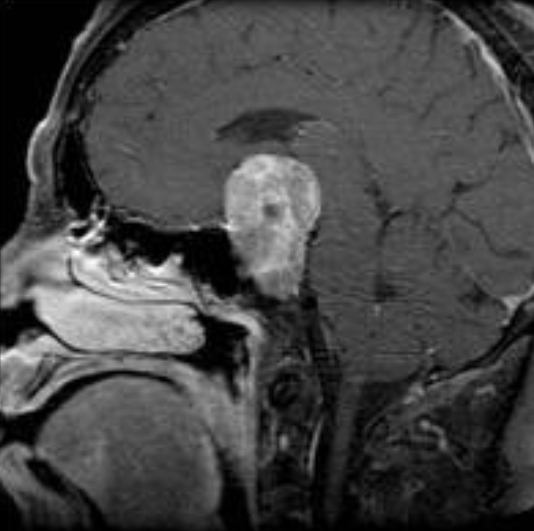

뇌하수체는 뇌의 정중앙부 하단에 위치하는 기관으로 신체 내 다양한 호르몬 분비를 조절하는 중요한 역할을 한다. 이곳에 발생하는 뇌하수체 종양은 동양인의 경우 평생에 거쳐 약 20%가 겪는다는 미국 존스홉킨스 의대의 연구결과가 있을 정도로 의외로 흔한 뇌종양(뇌암)이다. 뇌하수체 종양이 무엇인지 자세히 살펴본다.

호르몬 분비에 영향을 주지 않는 비기능성 종양도 크기가 커진다면 주변기관을 압박하거나 뇌하수체 조직으로 가는 혈액흐름을 저하시켜 증상을 일으킬 수 있다.

특히 뇌하수체 주변에는 시신경‧시교차‧내경동맥‧해면정맥동‧측두엽이 위치해 이와 관련된 여러 증상이 나타날 수 있다. 종양이 주변 시신경을 압박한다면 시력이 나빠지거나, 바깥쪽의 시야가 희뿌옇거나 검어지는 시야장애가 생길 수 있다. 주변 혈관이 압박받으면 두통이 발생하며 뇌척수액이 지나는 길을 막으면 뇌 안에 물이 차는 수두증도 나타난다.

이렇게 종양의 크기가 커지거나 기능성 선종일 때는 수술치료와 방사선치료, 약물치료 등의 항암요법을 고려할 수 있다. 일반적으로 시야장애는 즉각적인 수술을 통해 압력을 낮추면 90%까지 회복되며 뇌하수체 기능 저하도 정상으로 돌아올 수 있다.